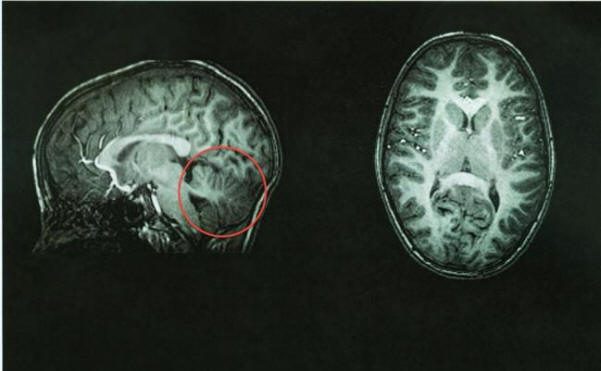

Tomografia cerebrale normale, cervelletto in rosso

Dopo la tomografia, i medici hanno immediatamente identificato la fonte del problema: la sua il cervelletto era assente. Lo spazio in cui dovrebbe essere vuoto. questo fornisce l’area cerebrale piena di liquido cerebrospinale protezione contro la malattia. Il cervelletto impiega circa il 10 percento di volume totale del cervello, ma contiene il 50 percento dei neuroni.